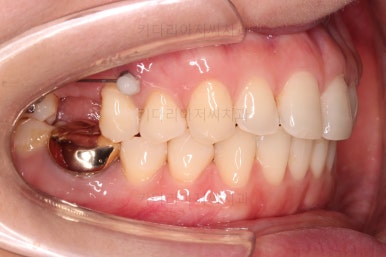

어금니쪽은 쓰러진 어금니를 원위치 시키기 위해서 미니스크류를 식립하여 준비작업을 해줍니다.

어금니 위치 조절을 계속 해주고요.

어금니도 원위치로 많이 갔네요.

아랫니 부분교정과 어금니 부분교정은 비교적 조기에 끝났으나(7개월) 임플란트가 생각보다 오래 걸렸습니다.

적절한 공간 확보 이후 해당 부분의 뼈가 너무 얇아 임플란트를 하기에 부적절했던거죠.

상악동 거상술 + 골이식을 광범위하게 꽤 많은 양을 하고, 한참을 기다립니다.

이후에 적절한 시기에 임플란트 식립을 하고 보철을 하고 마무리를 합니다.